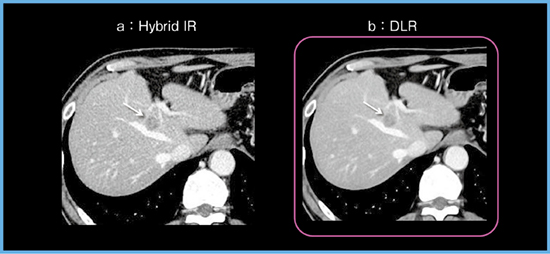

当院にて,まず「Aquilion ONE」を使用し,転移性肝腫瘍をターゲットに腹部CTにおけるDLRの初期検討を行った(解析当時はW.I.P.*)。結果として,Hybrid IR画像と比較し,DLR画像ではノイズが大幅に低減し,腫瘍を明瞭に描出できていた(図3)。詳細は割愛するが,DLRは腹部CT画像を定性的にも定量的にも改善しており,DLRは肝腫瘍検出能を向上させる可能性があると考えられた。

図3 直腸がんからの肝転移症例(59歳,男性)